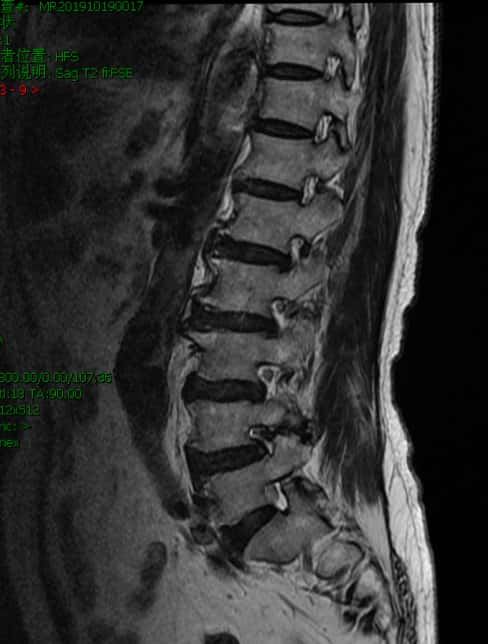

核磁上可见椎4/5间孔狭窄,神经根受压变形。

核磁上可见椎间孔狭窄,神经根受压变细。

这位老年患者有明确的手术适应症。和患者家属(内科专家)沟通后,最终决定采用切开减压内固定的办法。手术方案明确,手术时间可控。